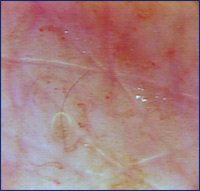

Video-capilaroscopia pré tratamento

Video-capilaroscopia  15 dias após fim do tratamento (12 sessões)